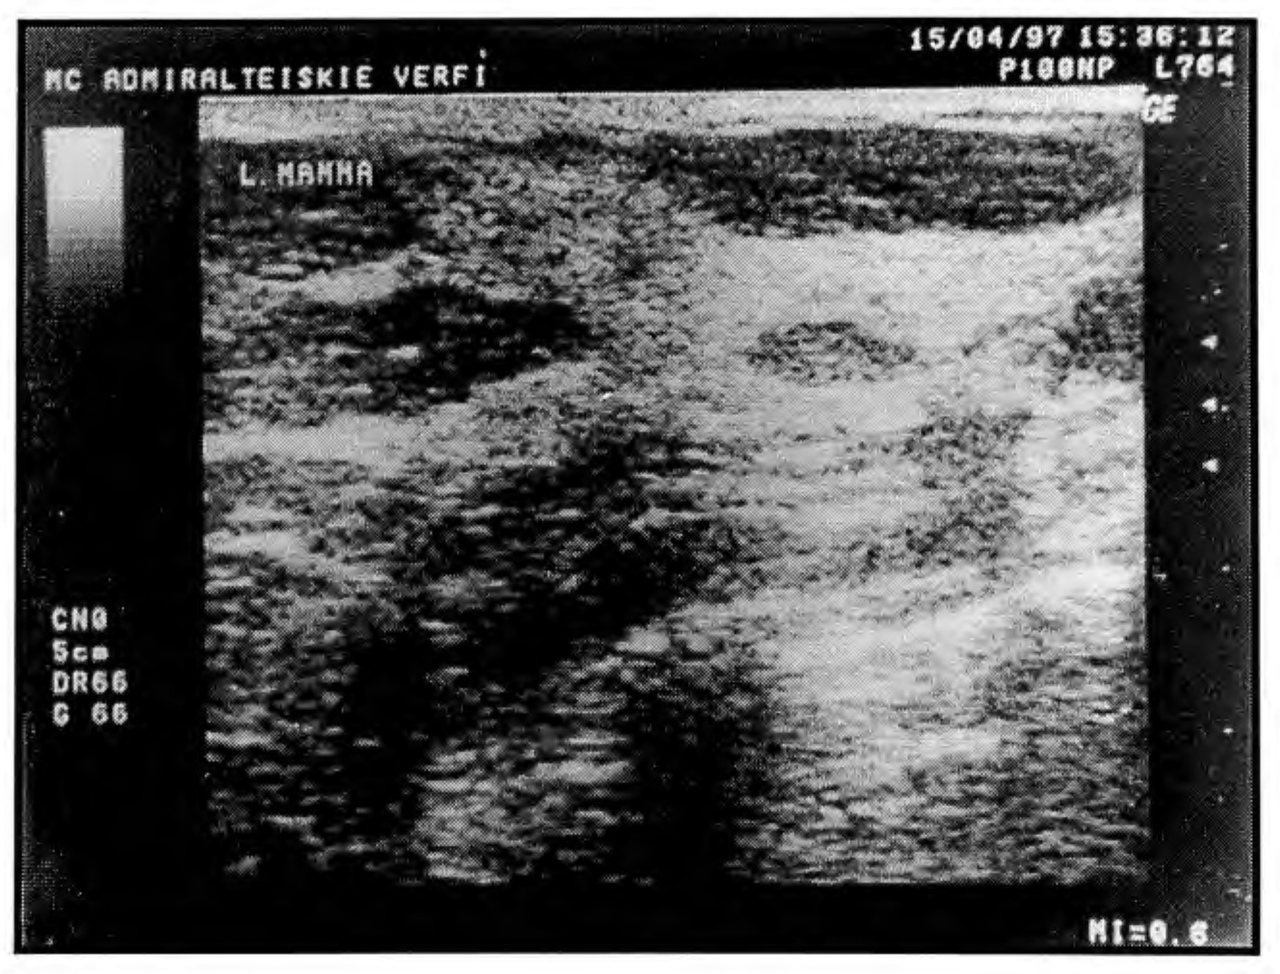

Исходя из этого можно сделать вывод, что в нормальной молочной железе сохранено гармоничное соотношение между фиброзной и железистой тканью и структура железы физиологически соответствует возрасту (рис. 3,4,5) железистой ткани от 15 до 33 мм, а показатели эхоплотности не соответствовали возрасту.

Рис. 3. Эхограмма молочной железы пациентки 25 лет. Репродуктивный тип строения. Толщина слоя железистой ткани - 14 мм. Показатели эхоплотности - средние (26-28). Явлений возрастной инволюции нет.

Рис. 4. Эхограмма молочной железы пациентки 45 лет. Предменопаузальный тип строения. Толщина слоя железистой ткани - 10 мм. Показатели эхоплотности - повышенные (35-37). Явления возрастной инволюции - в виде частичной жировой трансформации железистой ткани.